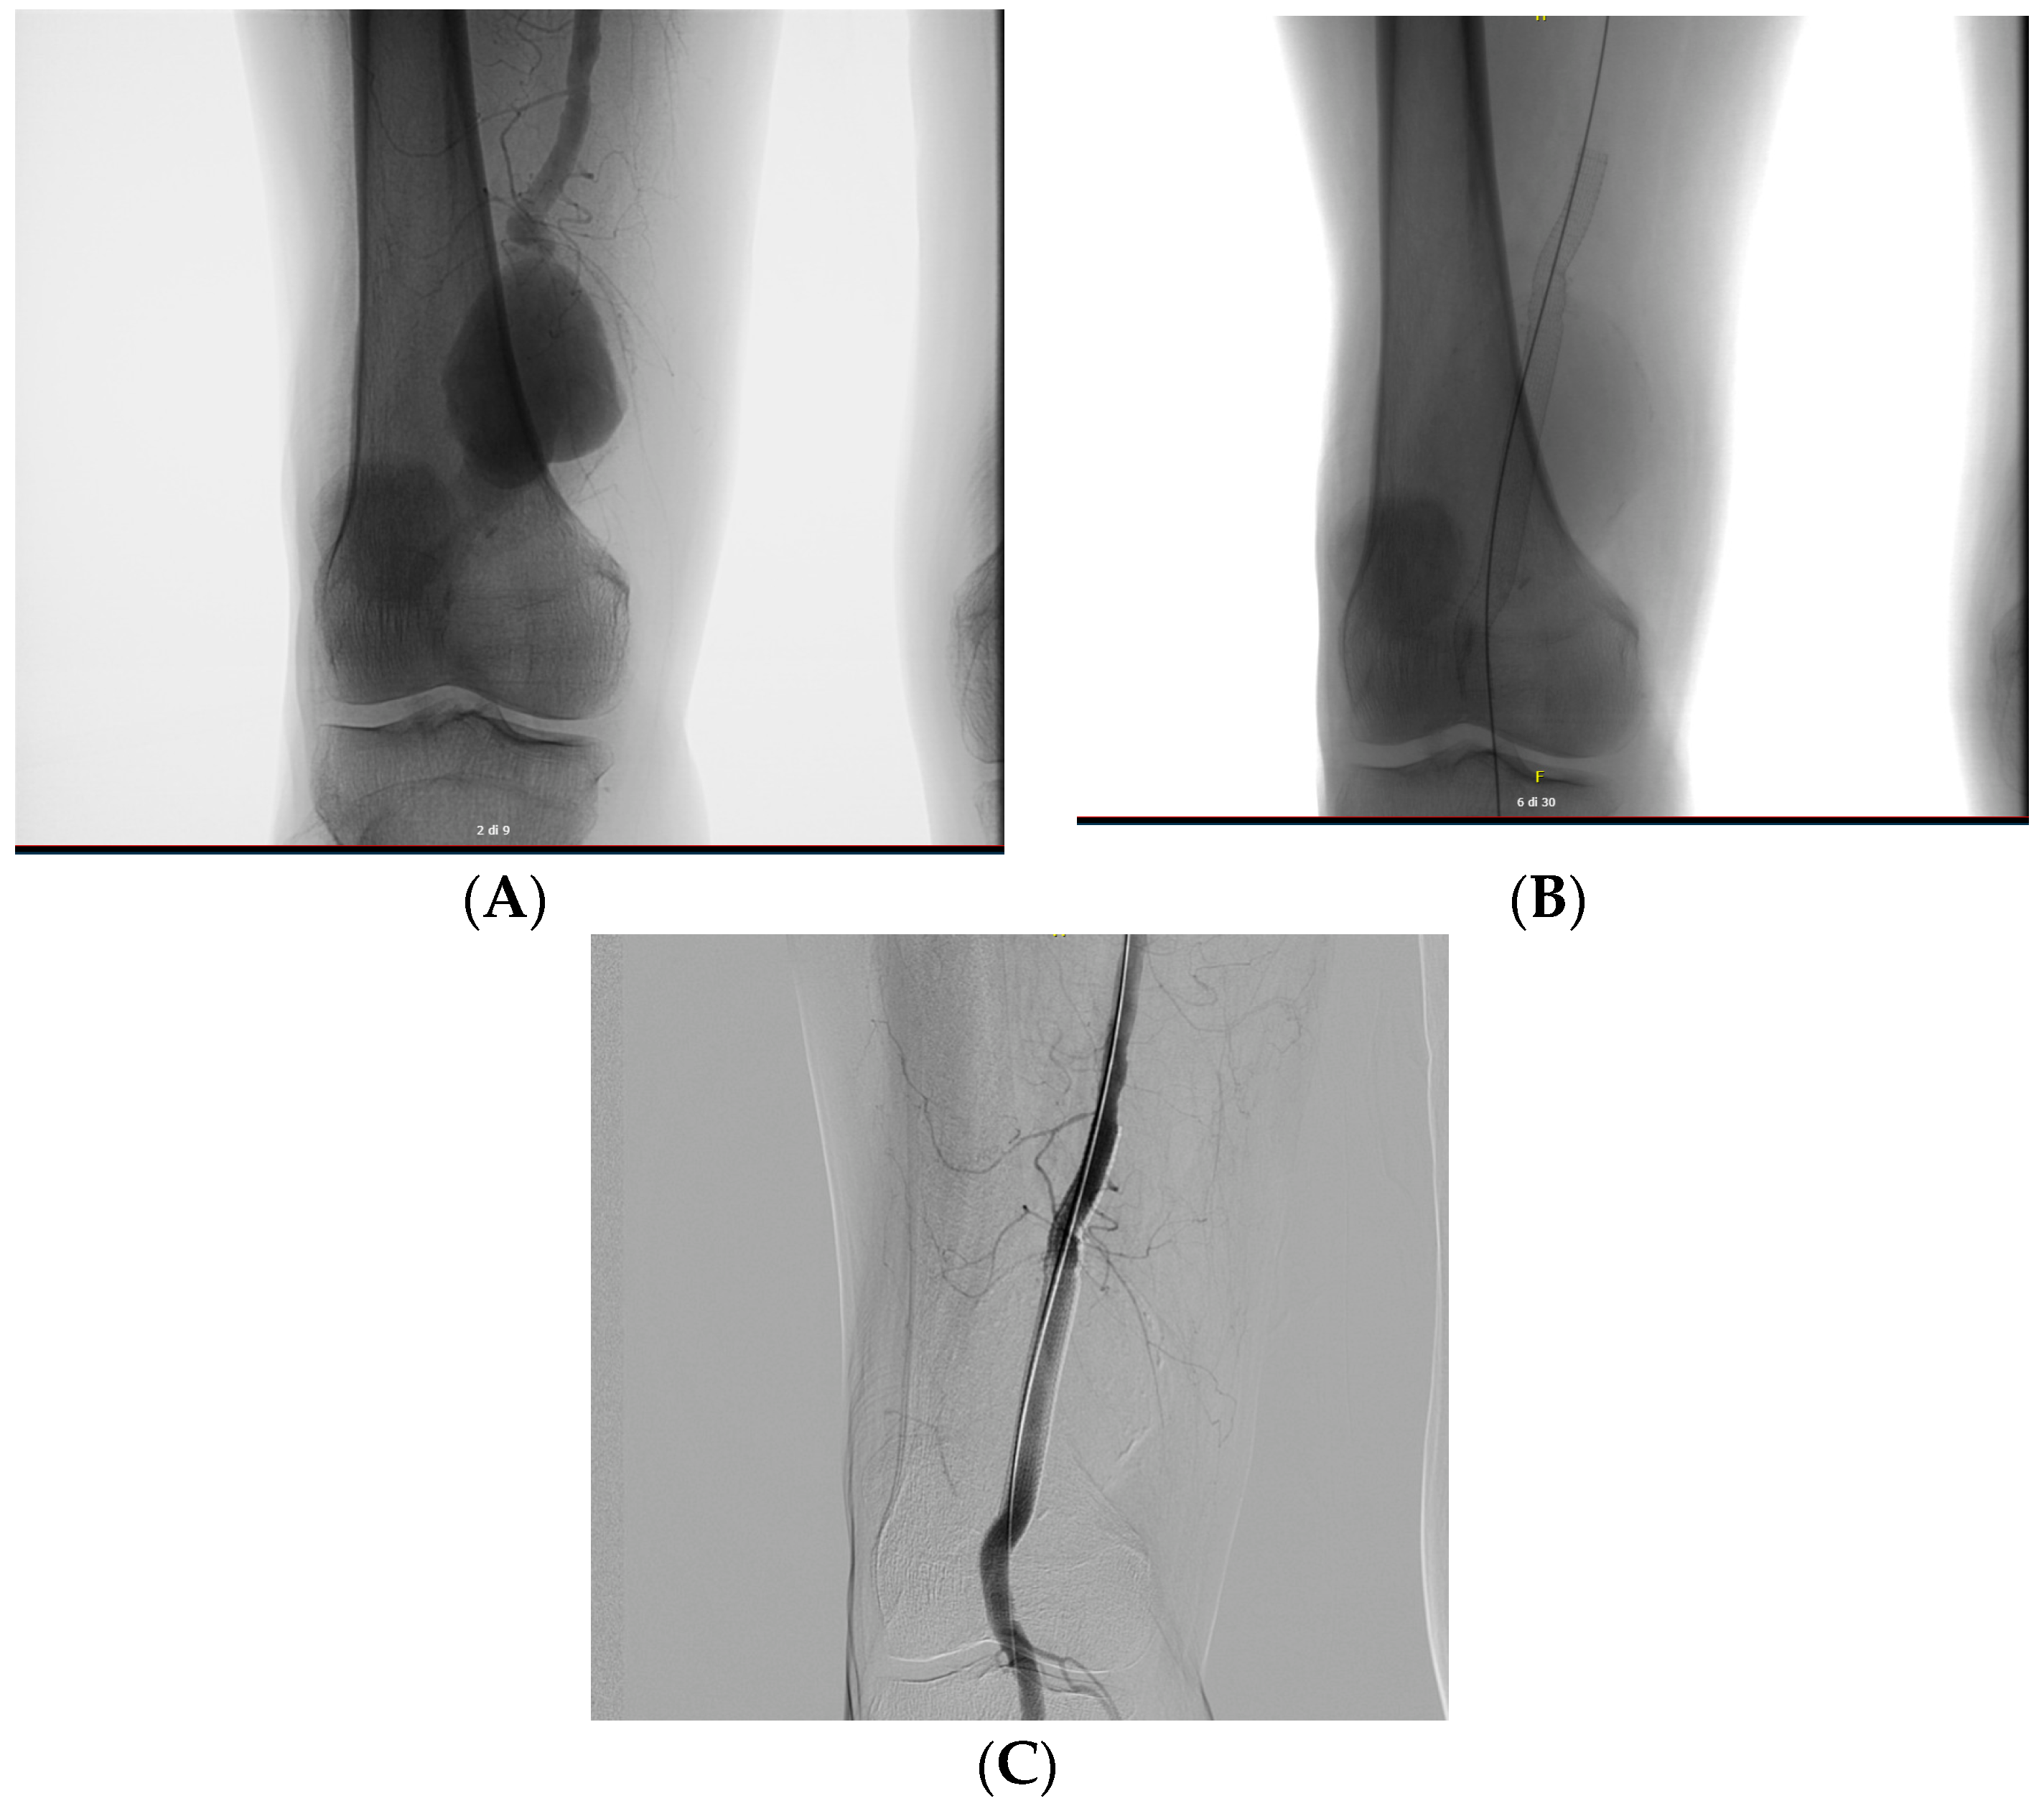

A 69-year-old patient with hypertension, BPCO and diabetes mellitus comes to the outpatient clinic complaining of free walking intervals of less than 50 m on flat ground, with associated cramping pain in the thigh and calf. Control ECD is performed which shows demodulated flow downstream of the iliac artery with velocimetry less than 30 cm/sec systolic peak. A control CT is requested which confirms a Leriche syndrome characterised by bilateral iliac stenosis with increased calibre of the lumbar arteries, left and right iliac stenosis and aortic stenosis. From a surgical point of view, we opted for ultrasound-guided puncture on the left side with placement of the 7 fr introducer on the right and left side in the common femoral artery. Angiography was performed with evidence of multiple stenosis on the iliac and external bilaterally involving the aortic carrefour. Viabahn8 × 50 mm stents were placed on the right and s common iliac and 7 × 100 mm and 7 × 50 mm Viabahn stents were placed on the right and s external iliac, respectively. Remodelling was performed on 7 × 80 and 6 × 60 Mustang flask. The final check showed perveity of the right hypogastric.

Figure A3. Multiple stenosi observed with angiography (A) and follow up post-operative (B).